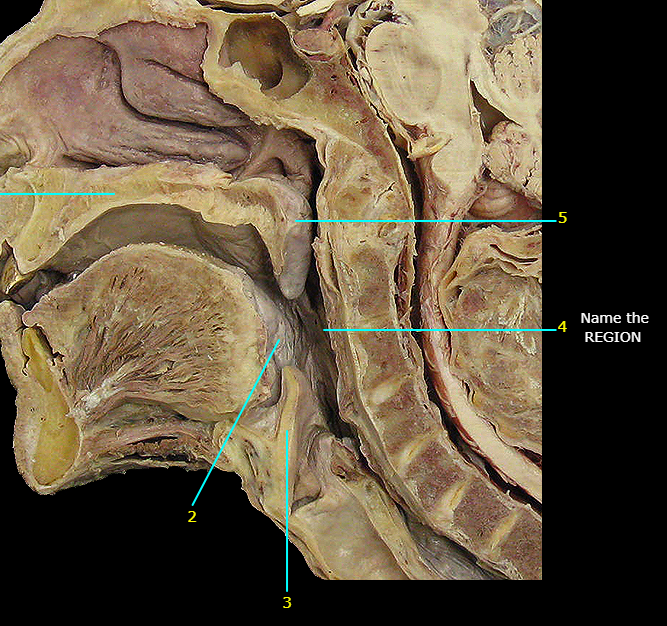

Name #3

Epiglottis (epiglottic cartilage)

Name the bottom structure

Thyroid cartilage

Name the structure

Laryngeal prominence

Name the blue structure

Arytenoid cartilages

Name the yellow structure

Cricoid cartilage

Cricothyroid joint